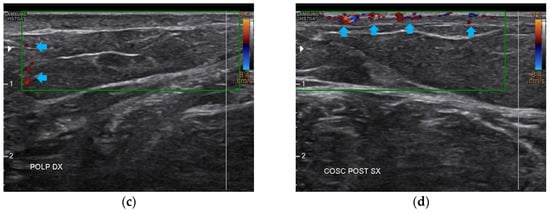

3.2. Imaging Evaluations After the Treatment